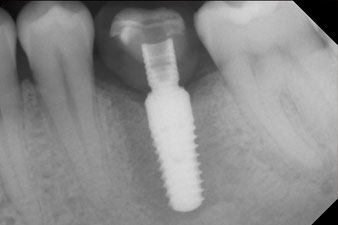

Implantat

Abb. 3: Nach Aufbereitung mit dem Implantmed Implantologiemotor wird ein Implantat (Durchmesser 4 mm, Länge 12 mm) bei einem Drehmoment von 43 Ncm maschinell eingeschraubt.

Nach gründlicher Entfernung des Granulationsgewebes wurde das Implantat wie geplant eingebracht (blueSky, bredent).

Das Drehmoment beim maschinellen Einbringen war 43 Ncm. Zusätzlich wurde, nach Einschrauben eines speziellen, auf das Implantatsystem abgestimmten Mess-Pfostens (SmartPeg), der ISQ-Wert mit der Sonde des W&H Osstell ISQ Modul bestimmt.